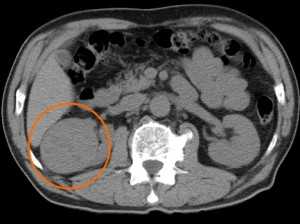

Типичный вид рака почки в нативную (до контрастирования) фазу. Хорошо заметен паренхиматозный узел в правой почке (в круге). Даже без усиления можно разглядеть его неоднородную структуру - с преобладанием мягкотканного компонента, а также с наличием менее плотных участков и включений кальция (красная стрелка).